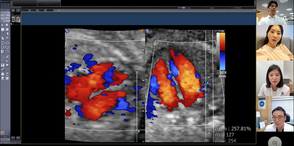

세브란스병원, 산모 맞춤형 ‘스마트 맘 케어’ 플랫폼 개발